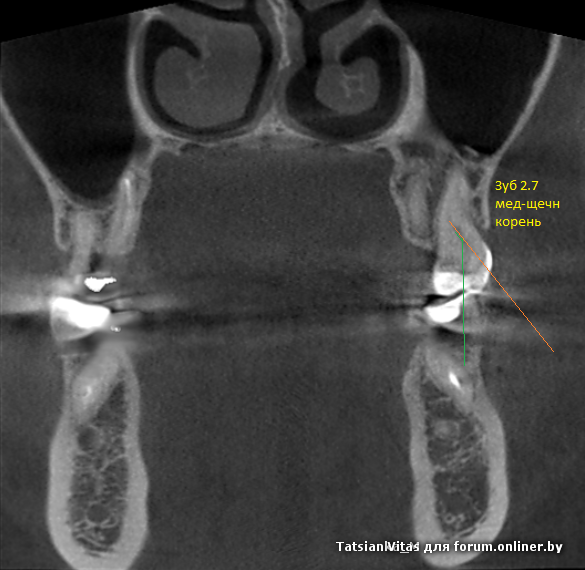

Поясню по ситуации, что бы не сочувствовать о лечении в ноу нейм клинике и почему микроскоп не панацея.

Вход в канал находился ниже устья на 5 мм внутри медиально щечного канала. Мне все таки удалось нащупать канал 08 инструментом изогнутым под 30-40 градусов, не не хватило времени его пройти, дальше бла-бла и т.д.

1. Найденный тактильно вход корреллирует с изображением? да/нет

по кт этот "типа срез" начинает место в медиально-щечном канале и уходит почти горизонтально в небный канал....

То изображение, что вы описываете, из расшифровки рентгенолога, ах-ха рентгенолог тоже "молодец", по нему на практике ничего не сходилось. Я про последнее изображение, каким-то чудом выцарапанное из моего КТ двадцать-пятым-по-счёту стоматологом, уже после описания "нащупанного" на практике.

На вашем рисунке, скажем, профиль мед-щечного корня, на этом изображении - анфас.

красным отмечен канал, который был найден и обработан, желтым - пропущенный